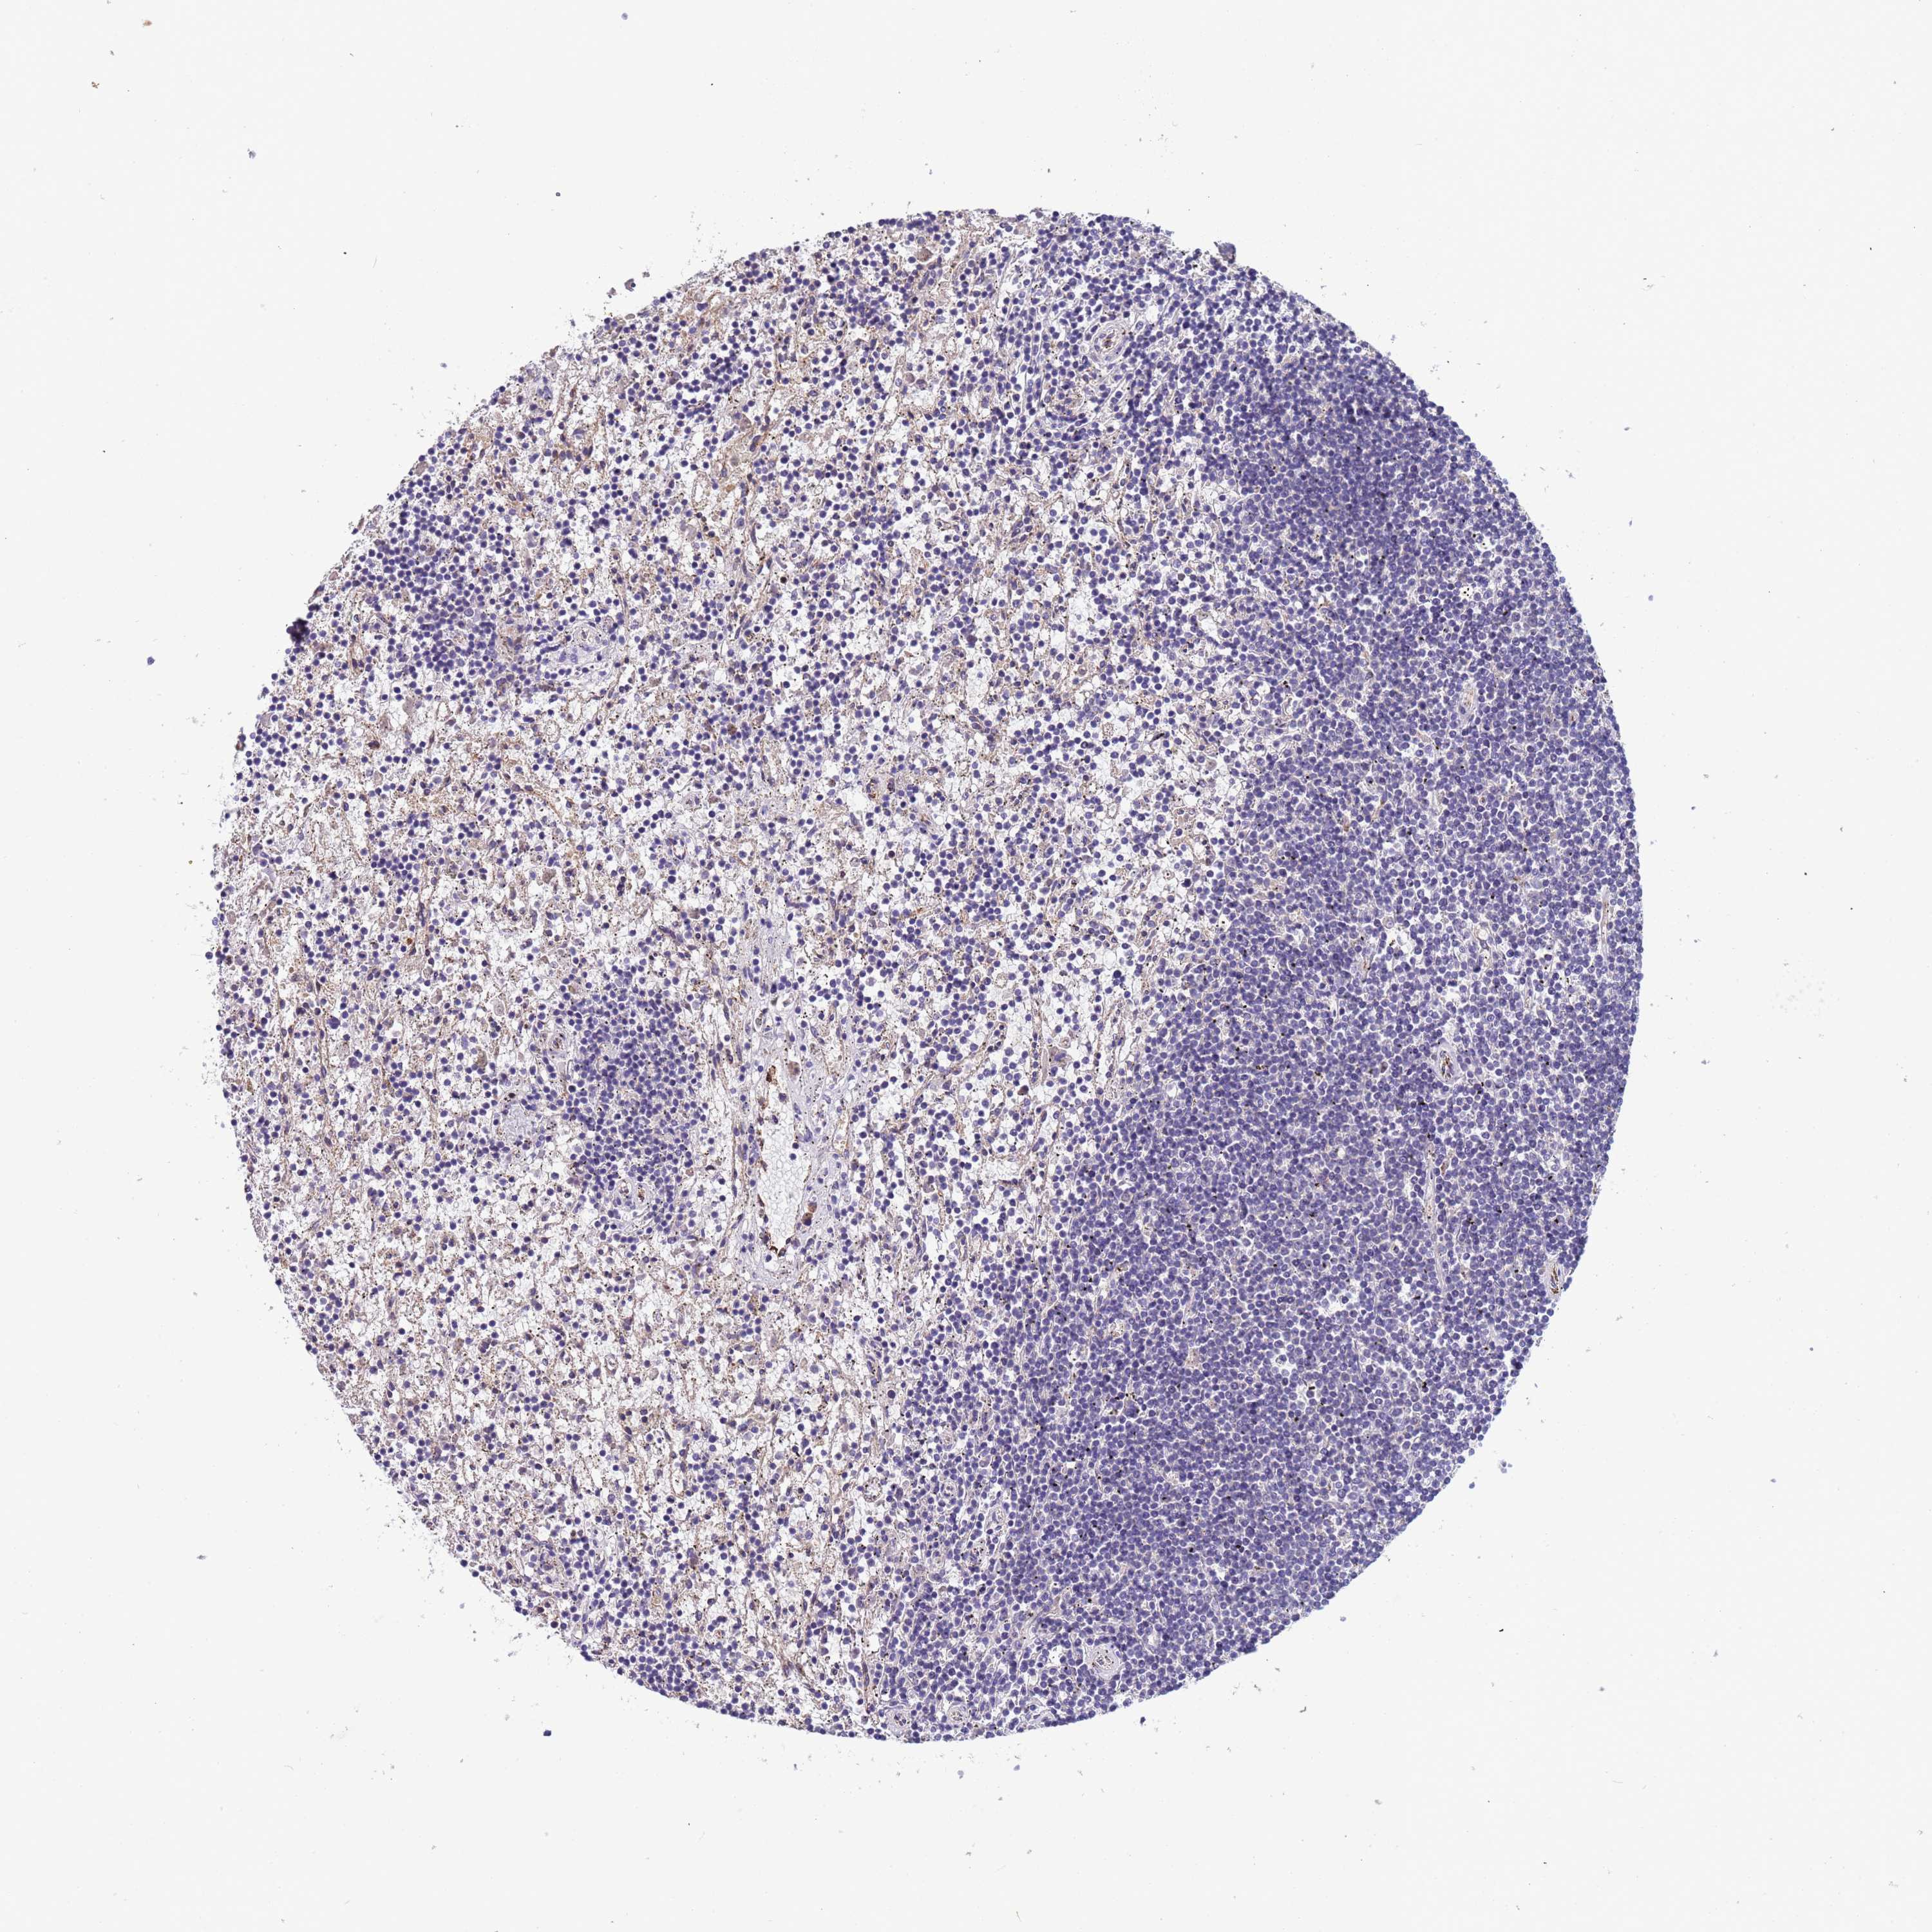

CANCER LYMPHOMA Show tissue menu

LYMPHOMA - Protein expressioni

A mouse-over function shows sample information and annotation data. Click on an image to view it in a full screen mode. Samples can be filtered based on level of antibody staining by selecting one or several of the following categories: high, medium, low and not detected. The assay and annotation is described here.

Each image is clickable and will lead to virtual microscopy that enables deeper exploration of all samples and also displays staining intensity scores, fraction scores and subcellular localization as well as patient and tissue information for each sample.

Hodgkin's disease, NOS

Malignant lymphoma, non-Hodgkin's type, High grade

Malignant lymphoma, non-Hodgkin's type, Low grade